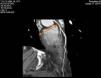

Due to persistence of symptoms, in 2012 exercise testing was repeated, which was positive for ischemia. In order to clarify the clinical picture, he was referred to our hospital for cardiac computed tomography (CT) angiography. This showed a zero calcium score (Figure 1), corresponding to the 25th percentile for age and gender, and revealed 50–70% stenosis with a non-calcified eccentric plaque in the distal left main/proximal anterior descending artery (Figure 2).